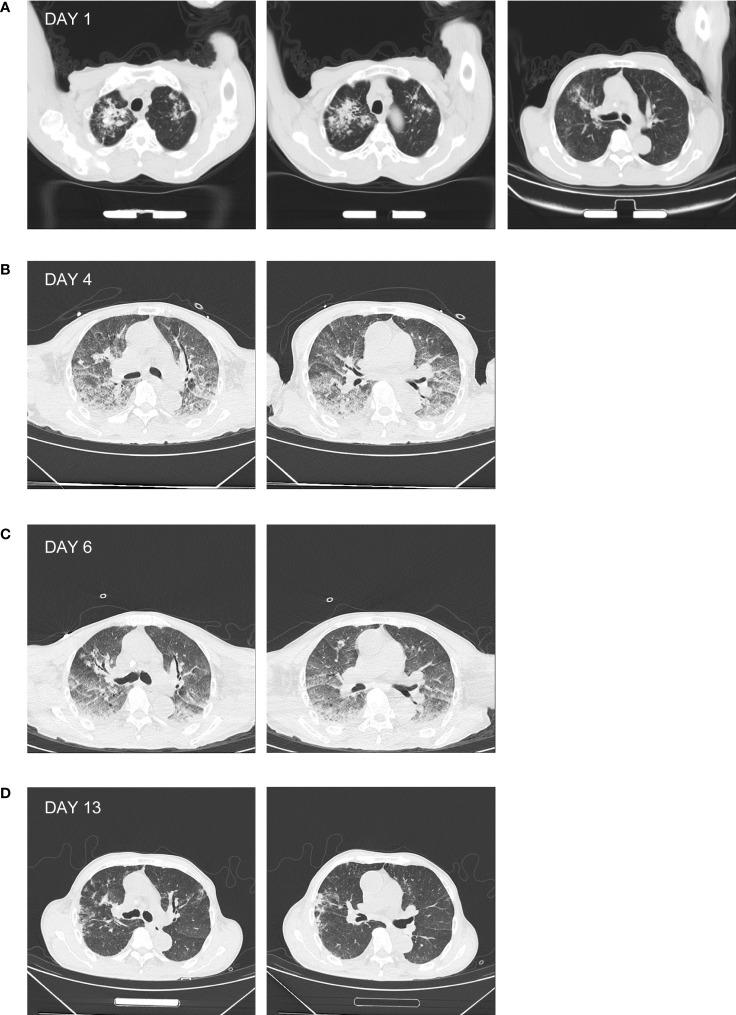

Leptospirosis is a zoonotic infection caused by the pathogenic . Leptospirosis is transmitted mainly through contact with contaminated rivers, lakes, or animals carrying . Human leptospirosis has a wide range of non-specific clinical manifestations ranging from fever, hypotension, and myalgia to multi-organ dysfunction, which severely hampers the timely clinical diagnosis and treatment of leptospirosis. Therefore, there is an urgent clinical need for an efficient strategy/method that can be used for the accurate diagnosis of leptospirosis, especially in critically ill patients. Here, we report a case of a 75-year-old male patient with clinical presentation of fever, cough, and diarrhea. Initial laboratory tests and a computed tomography (CT) scan of the chest suggested only tuberculosis. The patient was finally diagnosed with pulmonary tuberculosis (PTB) combined with leptospirosis by sputum Xpert MTB RIF, epidemiological investigations, and delayed serological testing. Furthermore, through metagenomic next-generation sequencing (mNGS) of clinical samples of cerebrospinal fluid (CSF), urine, plasma and sputum, the causative pathogens were identified as complex and spp. With specific treatment for both leptospirosis and tuberculosis, and associated supportive care (e.g., hemodialysis), the patient showed a good prognosis. This case report suggests that mNGS can generate a useful complement to conventional pathogenic diagnostic methods through more detailed etiological screening (i.e., at the level of species or species complex).